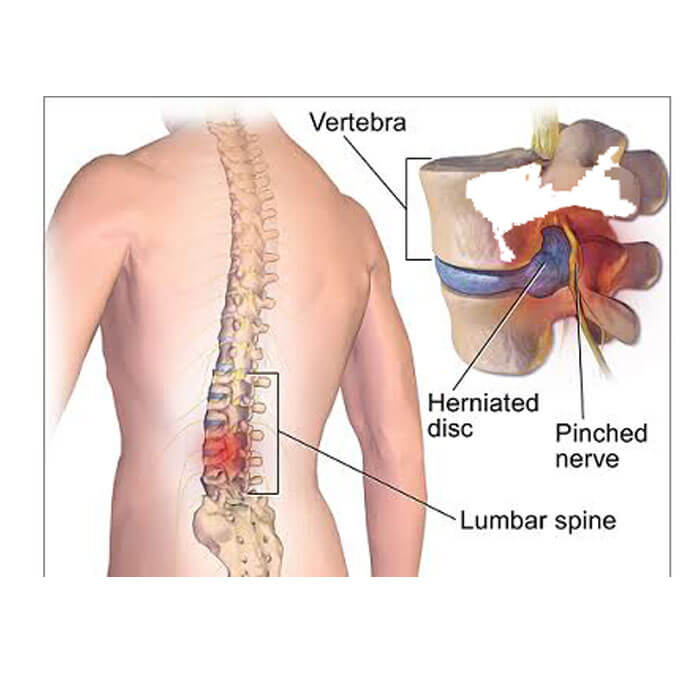

When someone comes to us with extremity symptoms, we almost always suggest they first get an evaluation with their primary care physician. If a person is experiencing low back pain or neck pain, we will usually watch them over time and encourage them to maintain good, stable physical activity to see if the issue resolves. If the issue is not resolving with physical activity, over the counter treatments, or pain management and anti-inflammatory medication, the next step would be to see a doctor for an evaluation.

The only two things that are really proven to help a patient who is experiencing problems with their spine are time and surgery. Everything else is used to manage symptoms while your body fixes it naturally. If your body doesn’t fix it, then surgery becomes a good option.

The vast majority of patients with spine problems can be treated in a conservative and non-surgical fashion. With very few exceptions, we recommend that all patients try physical therapy, home exercises, medication and often times spinal injections prior to considering surgery.

If the person has problems with their spinal cord, has significant weakness in an arm or leg or limb, or if they have tried all of the conservative treatments and have been unsuccessful, we might recommend they go directly to surgery.